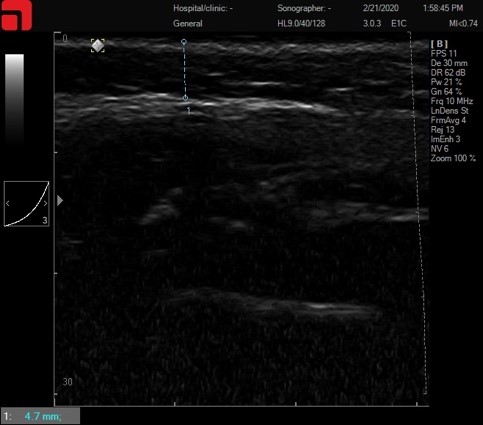

Сканирование субментальной области

Рис. 1. Сканирование субментальной области.

Главная задача данной точки сканирования – определить, на какой глубине располагается тело нижней челюсти (corpus mandibulae) в наиболее выступающем участке, по нижнему краю (Рис.2.). Этот замер необходим для определения нижней границы работы для безопасного проведения процедуры. В данном случае надкостница начинается на глубине 3 мм, следовательно, нижняя граница для лифтинговых насадок (3 мм M7 и 4,5 мм D4) должна располагаться выше, чтобы не травмировать надкостницу. На данном участке можно работать манипулой 1,5 мм S7.